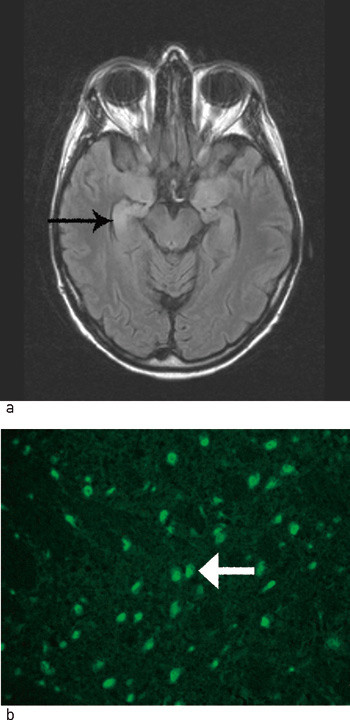

Ved innkomst var pasienten mentalt upåfallende og fullt orientert. Somatisk status var normal. Ved nevrologisk undersøkelse var det nedsatt følelse distalt i venstre sides ekstremiteter, ellers var det normale funn. MR-undersøkelse av hjernen ved innkomst var normal. Undersøkelsen ble gjentatt noen uker senere og viste da intens kontrastoppladning i høyre hippocampus og amygdala samt ødem og hyperintensitet i samme område på T2-vektet undersøkelse (fig 2a). EMG/nevrografi viste venstresidig sensorisk aksonal nevronopati. Celletallet i spinalvæsken var lett øket (10 mononukleære celler/mm³), og det var > 10 oligoklonale IgG-bånd ved isoelektrisk fokusering, men normalt spinalprotein. Hu-antistoffer ble påvist både i serum (titer 8000) og spinalvæske (titer 1000) (fig 2b).